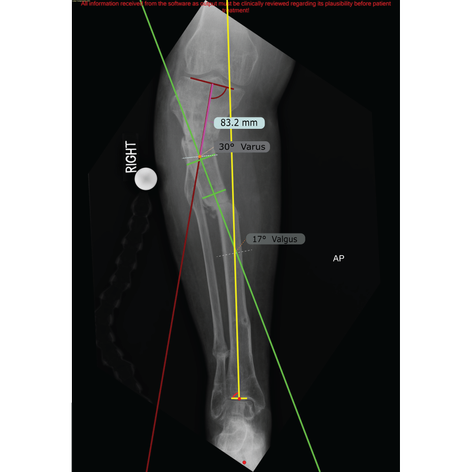

TSF ALLY is a service to support surgeons with the deformity analysis and case planning for patients selected for TAYLOR SPATIAL FRAME◊ External Fixator surgery.

Engineers trained in deformity correction use TraumaCad® to analyse the deformity, create a TSF plan and generate a case in smart-TSF.com. The suggested TSF construct will be optimised, with the aim of minimising Strut change-outs during correction.